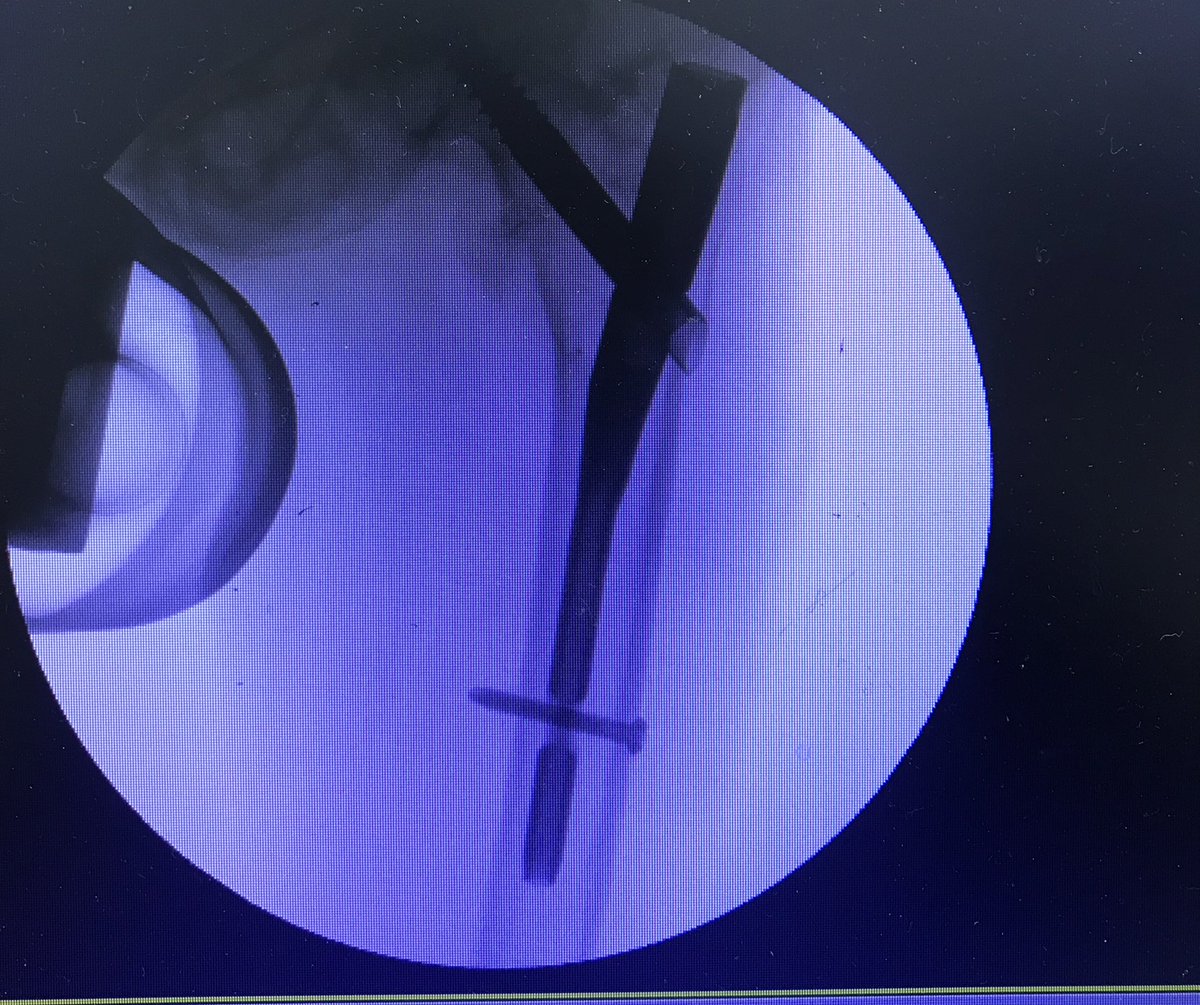

We made a lot of noise today at the orthopedic surgery workshop, diving deep into internal and external fixation techniques!

Once again big thanks to our amazing supervisors and team who made this possible!

@anas_nooh

@BayanTash

@AltaibOla

@ Mahmoud

Ortho power 🦴🔥